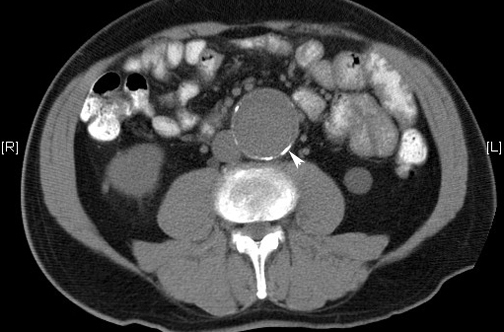

La tasa de cirugías para reparación electiva del aneurisma abdominal en EEUU duplica la de Inglaterra, pero la mortalidad por rotura aneurismática es tres veces menor. New England Journal of Medicine, 24 de noviembre de 2016